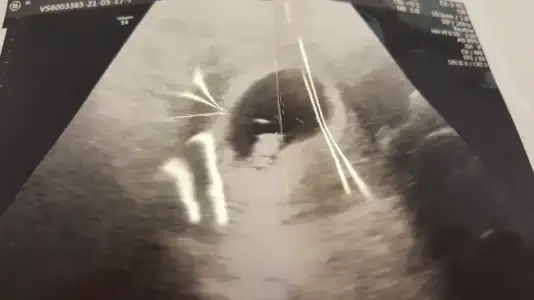

Sağ olasın. Ben göremedm ama şüphen devam ediyorsa kanda baktır bi istersen?